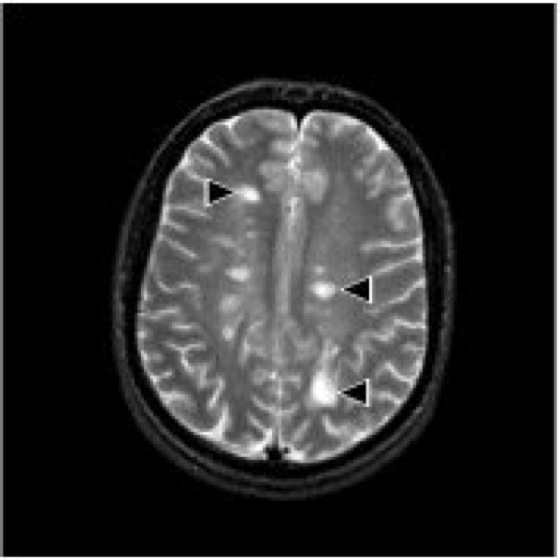

Mitte der 1970er Jahre wurde in größerem Umfang die Computertomographie (CT) in die klinische Diagnostik eingeführt. Hiermit war es erstmals möglich, das Gehirn des Menschen bildgebend darzustellen. Die Tatsache, daß die Computertomographie Röntgendichteunterschiede abbildet, hat allerdings zur Folge, daß sich Krankheiten, die nicht mit solchen Unterschieden einhergehen, im CT nicht abbilden. Teilweise können hier durch die Gabe von Kontrastmitteln, die sich beispielsweise in Tumoren anreichern, Verbesserungen erzielt werden. Die etwa 10 Jahre später erfolgte Einführung der Kernspinresonanztomographie brachte wesentliche Verbesserungen, da hier für die Kontrastgebung der Wasseranteil in einem Gewebe eine wesentliche Rolle spielt. So lassen sich mit der Kernspinresonanztomographie z.B. die Entzündungsherde der multiplen Sklerose sichtbar machen ( siehe Abb. 5 ), die sich dem Nachweis mit der CT entziehen. Es ist so möglich, unter anderem Tumoren, Blutungen, Durchblutungsstörungen sichtbar zu machen. Mit der strukturellen Kernspinresonanztomographie läßt sich die Hirnanatomie in hervorragender Weise sichtbar machen. So läßt sich beispielsweise zeigen, daß bei Chorea Huntington der Nucleus caudatus (Caudatum), ein Teil der sogenannten Basalganglien, atrophiert ist. Ein vergleichbarer Befund fehlt bei der Alzheimer-Krankheit ( siehe Abb. 6 ). Die Kernspinresonanztomographie ist derzeit noch in ständiger Entwicklung. Neuere Verfahren lassen die Perfusion und die Diffusion von Wasseratomen nachweisen und eignen sich daher zur Frühdiagnostik von Hirninfarkten.

Abb. 6: Kernspinresonanztomographien bei einem Patienten mit Alzheimer-Krankheit und einem Patienten mit Chorea Huntington. Bei letzterem läßt sich eine Atrophie des (im Bild dunklen) Nucleus caudatus (Pfeil) als Grundlage der Erkrankung nachweisen.